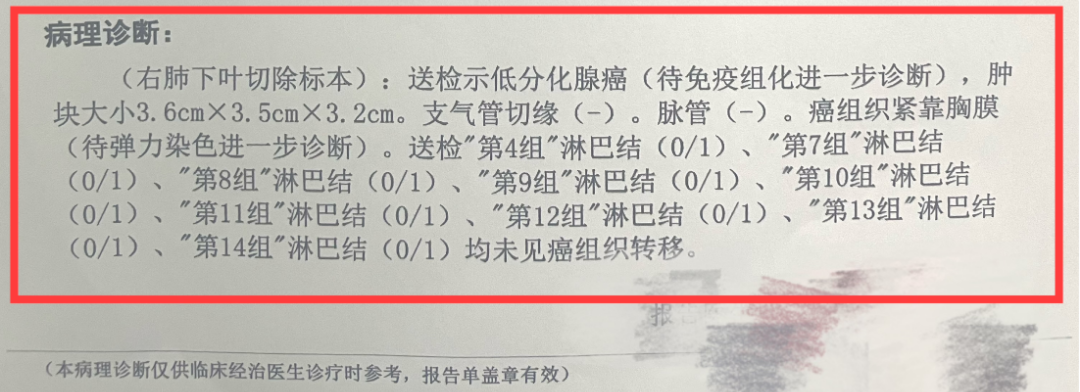

何志勇主任介绍,经过再次对肿瘤活检和检验检测,发现李先生仍然存在EGFR突变的肿瘤克隆。

“可能肿瘤还依赖EGFR信号通路,提高三代EGFR-TKI给药浓度是可能的有效方法之一。”

何医生介绍,三代EGFR-TKI伏美替尼由于化学结构上的优化,具备提高药物浓度而不增加副反应的可能,国内外有相似的研究报道。因此,建议李先生开始口服“双倍剂量伏美替尼”靶向治疗。令人欣喜的是,1个月后复查,李先生肺部及肝脏转移灶较前明显退缩,疗效评价达到部分缓解。

目前,李先生仍在口服“双倍剂量伏美替尼”治疗,肿瘤控制良好,已经维持稳定近一年,且并未有副作用,目前患者生活质量良好。